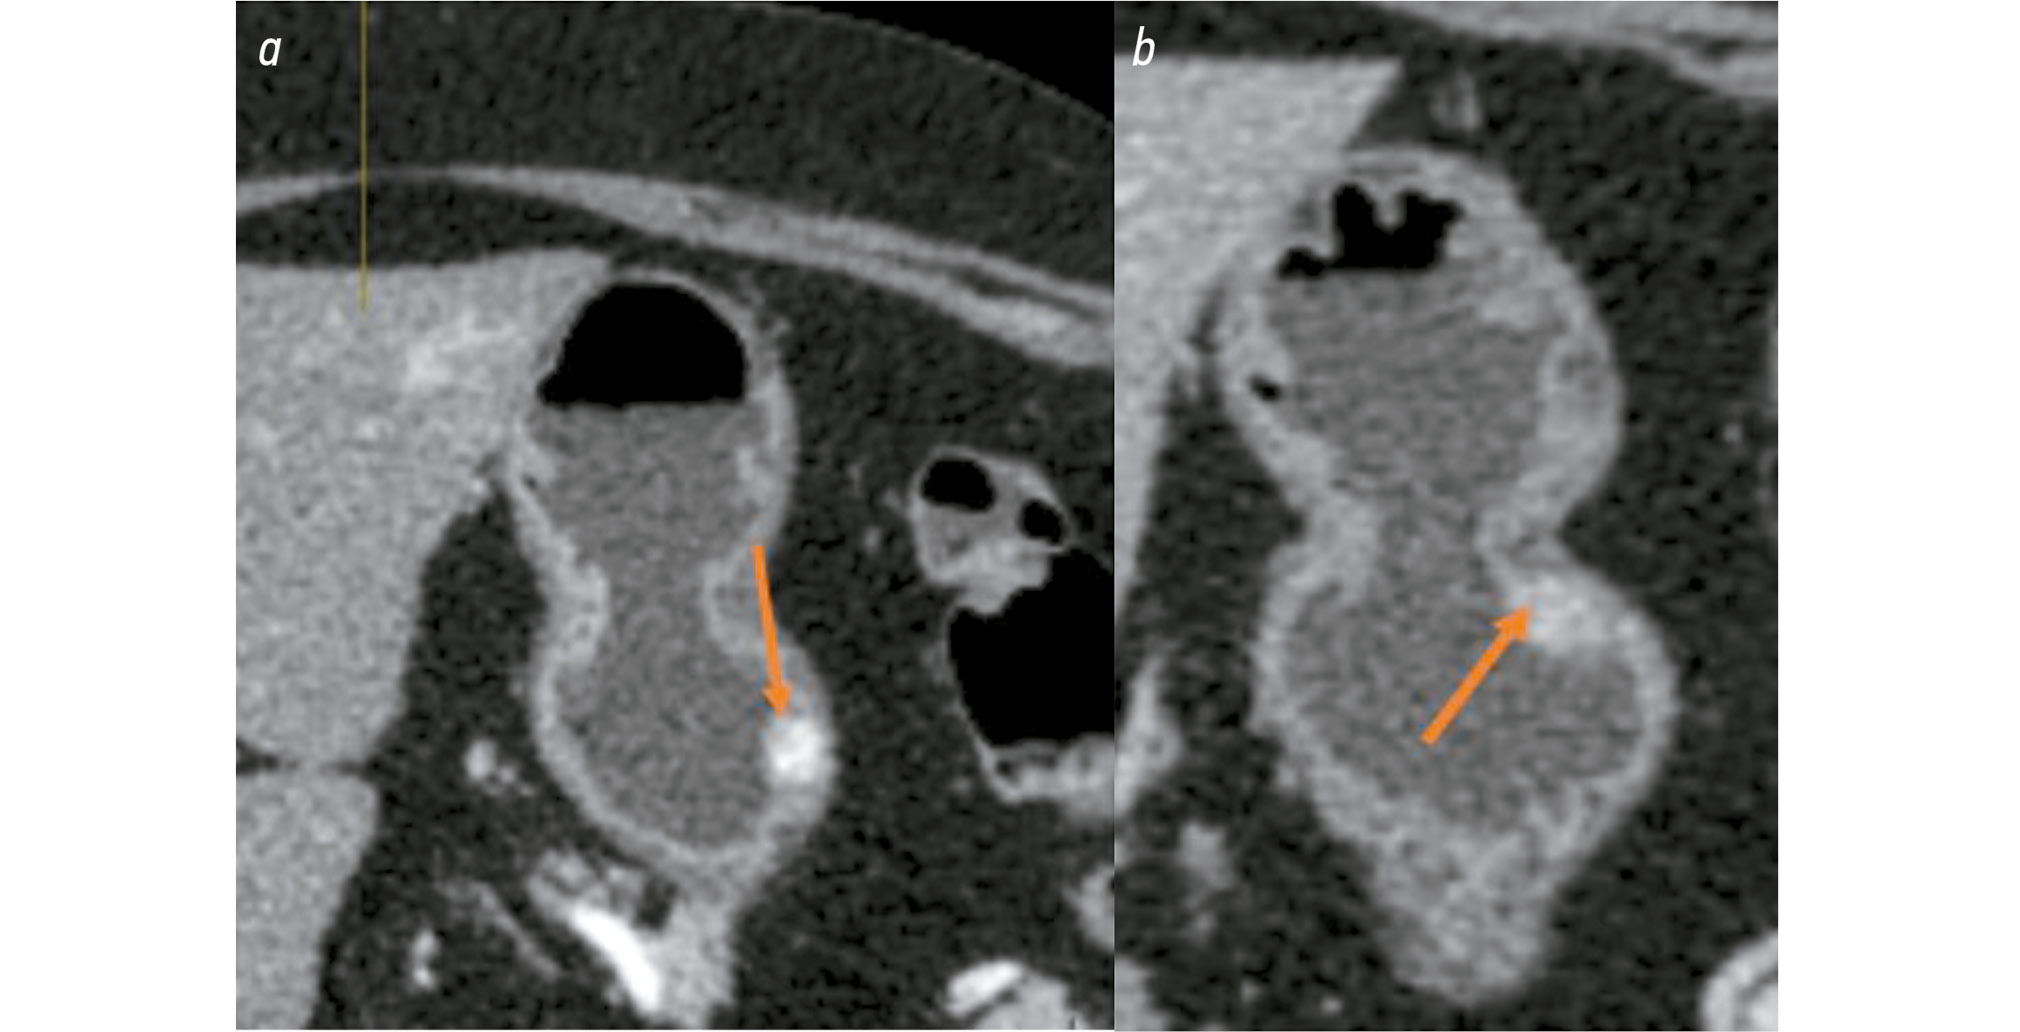

Some pancreatic NETs may appear hypovascular, requiring differentiation from other lesions such as serous cystadenomas, intrapancreatic accessory spleens, renal cell carcinoma metastases, and both cystic and solid masses, including hypovascular adenocarcinomas [13]. Fig. 2 presents a CT image of a pancreatic NET with these features. The lesion, located in the pancreatic body, is round with irregular margins, measuring approximately 2.3 × 2.1 cm, and contains a centrally hypodense area suggestive of necrosis [14]. It appears isodense relative to the pancreatic parenchyma in the venous phase and shows only mild enhancement during the arterial phase. There is no evidence of tumor infiltration into the surrounding fat or vascular structures. In this case, the tumor was identified based on indirect signs, including dilatation of the pancreatic duct, compression of the splenic vein, and moderate enlargement of the pancreatic body. This presentation is atypical for pancreatic NETs. Rare cases have been described in which venous phase enhancement is more pronounced [15].

Fig. 2. Computed tomography of a hypovascular pancreatic neuroendocrine tumor: a, a moderately hypervascular lesion in the pancreatic body with a hypodense central area and dilatation of the pancreatic duct, arterial phase (10th second); b, moderate compression of the splenic vein, venous phase.